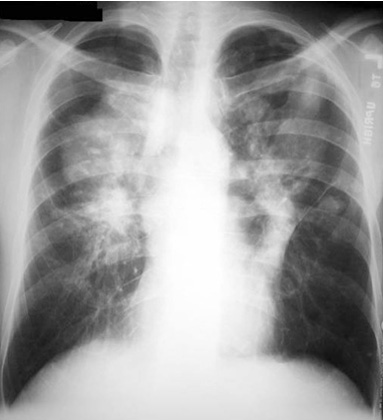

Bilateral upper lobe diseae.

Conglomeration of mass and fibrotic process.

Closely resembles Silicosis.